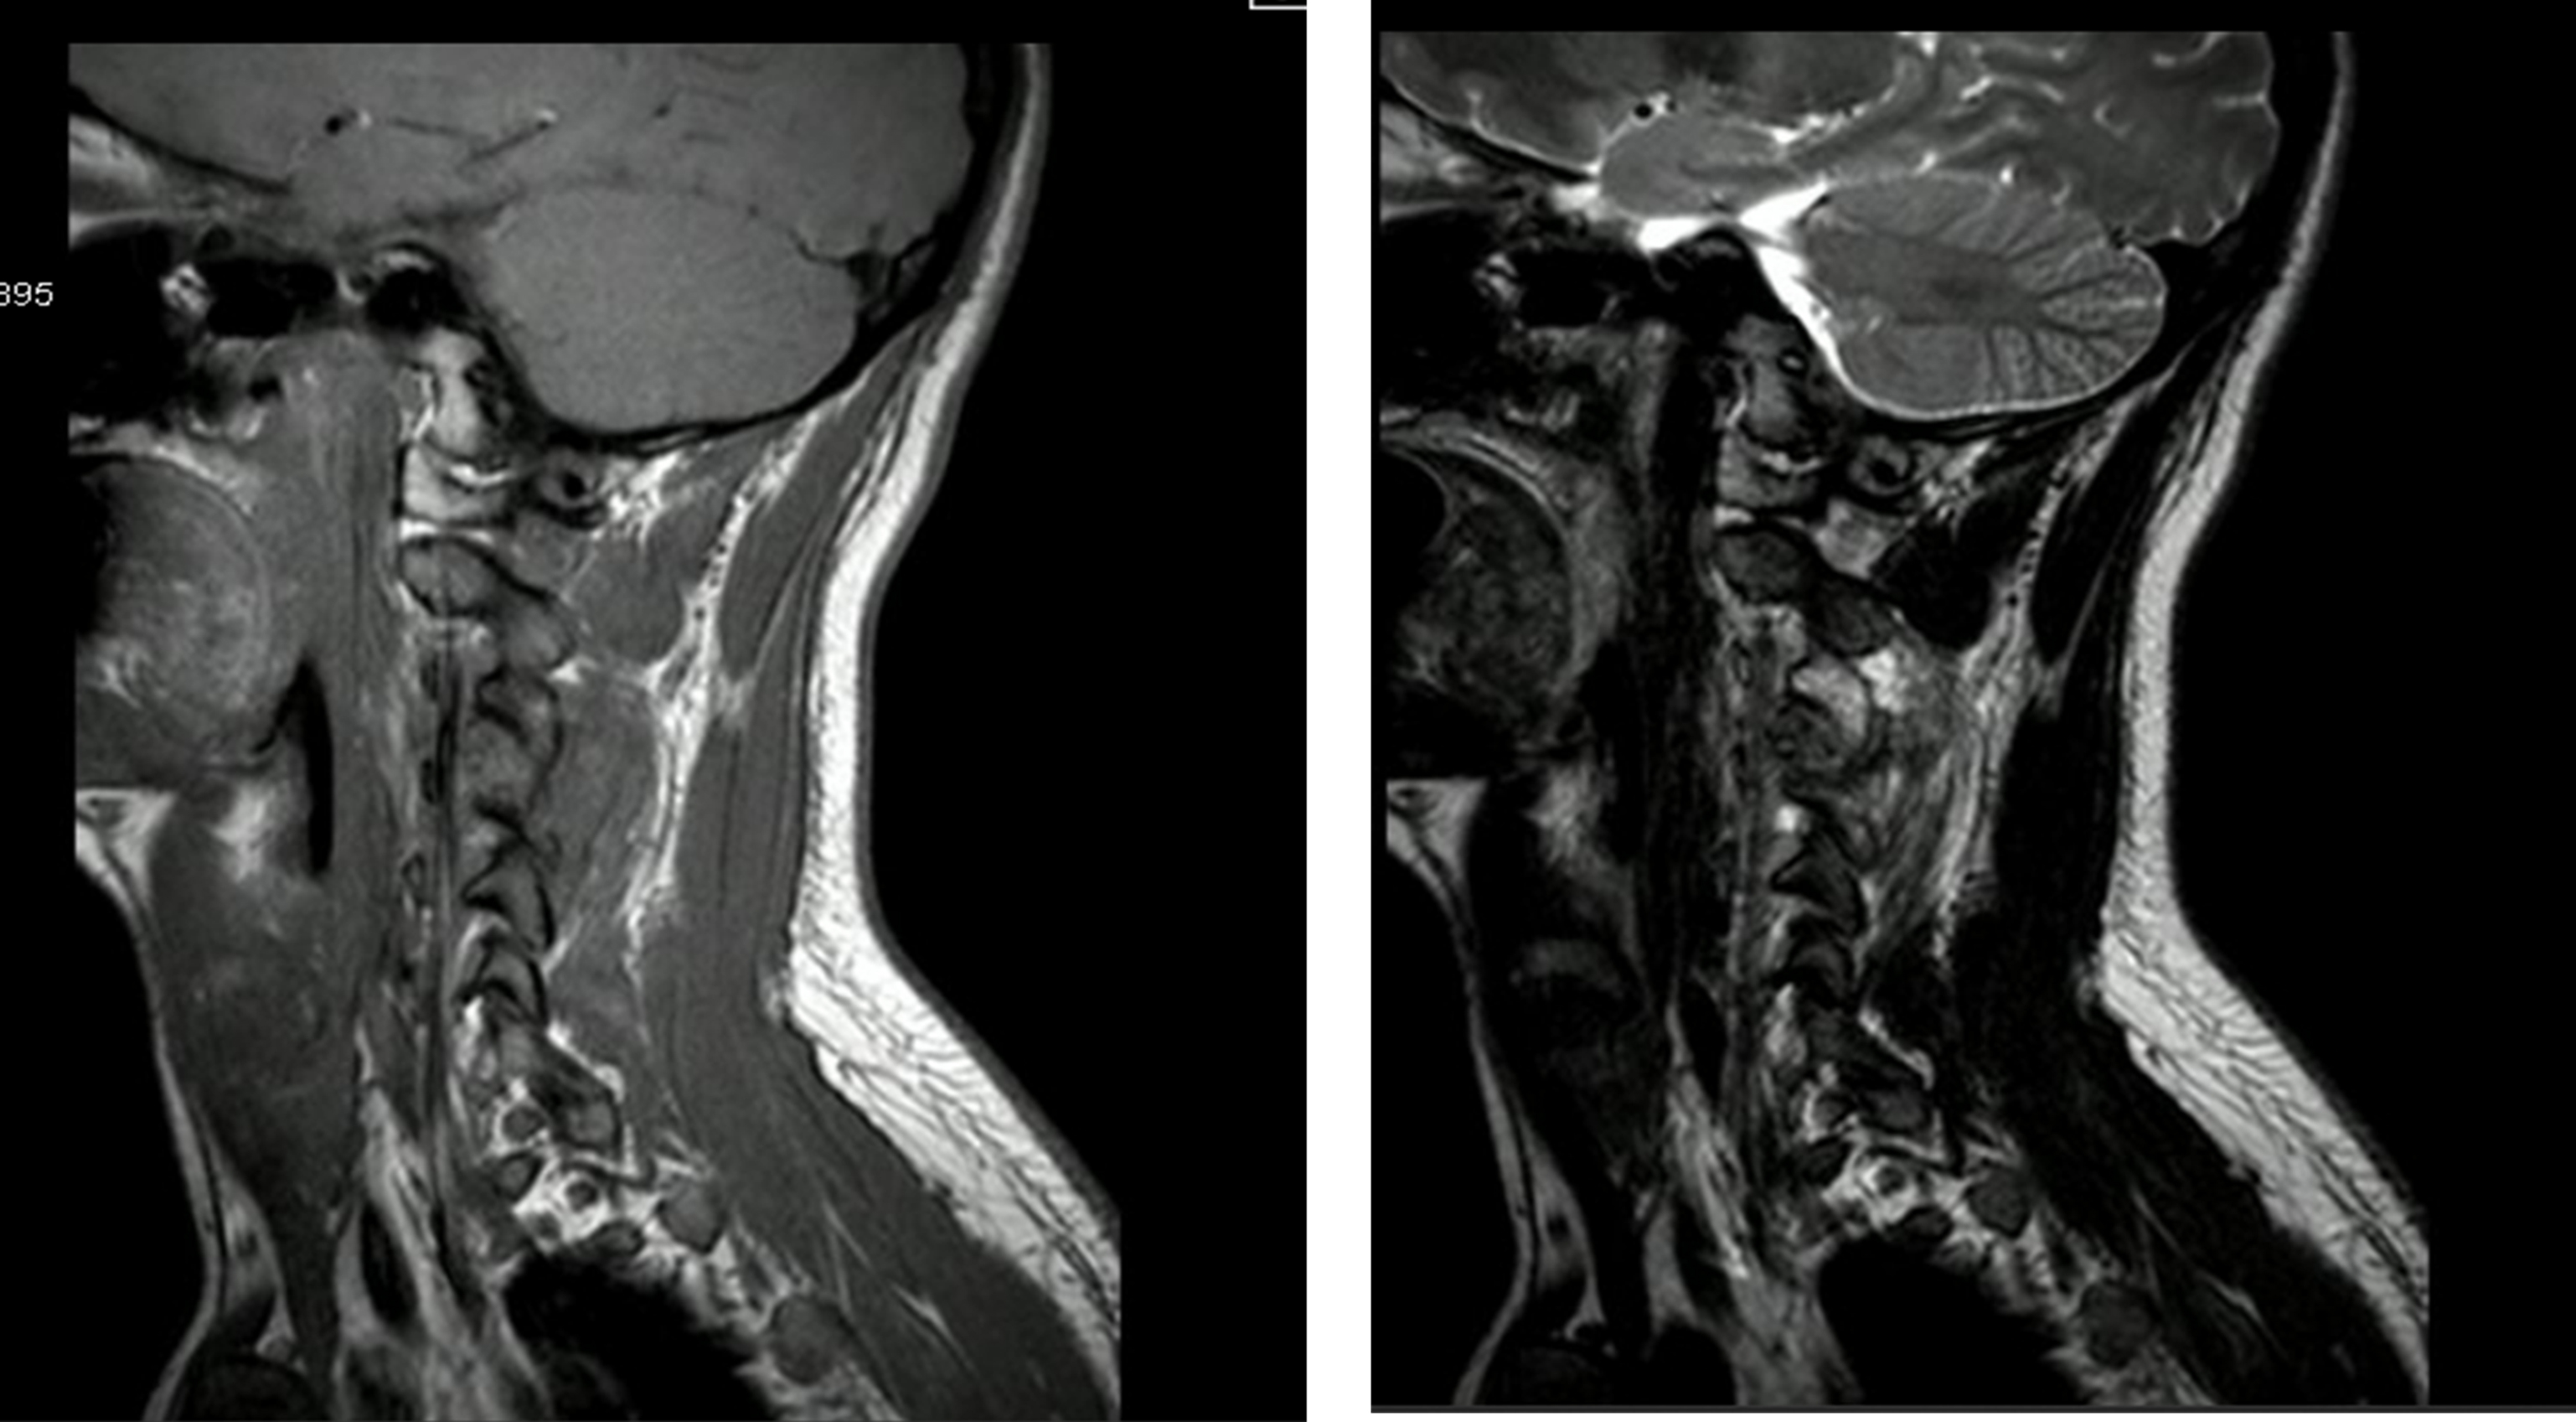

Resonancia magnética posquirúrgica (después de cirugía extrainstitucional)

Las imágenes tomadas revelan cambios posquirúrgicos de resección de masa en la apófisis articular superior izquierda de C4. Se observó una lesión expansiva de señal intermedia en T1, con realce algo heterogéneo con gadolinio, con medidas aproximadas de 14 × 16 × 17,5 mm, considerada primera posibilidad residuo o recidiva de la lesión. No se detalló alteración en la amplitud del canal espinal, con cuerpos vertebrales y discos intervertebrales sin alteraciones.

La imagen en T2 evidenció un aumento en la intensidad de señal de los músculos paravertebrales izquierdos entre C3-C4 y C4-C5, atribuidos a cambios por el procedimiento quirúrgico, relativamente reciente en el momento de toma de la imagen (figuras 4 y 5).